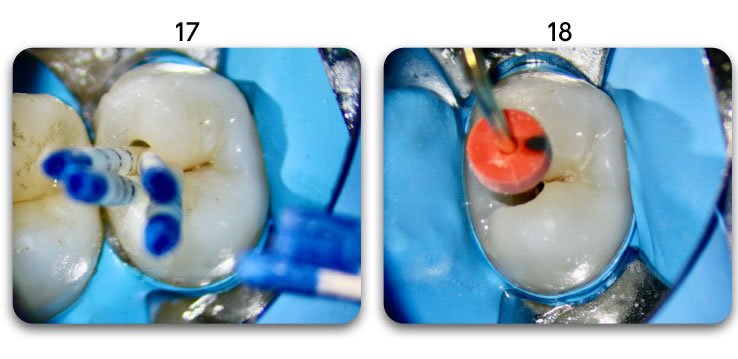

Excellent light transmission

Excellent light transmission for use with dual-cure resins, Biolight DUAL offer excellent light transmission through the optic fiber material.